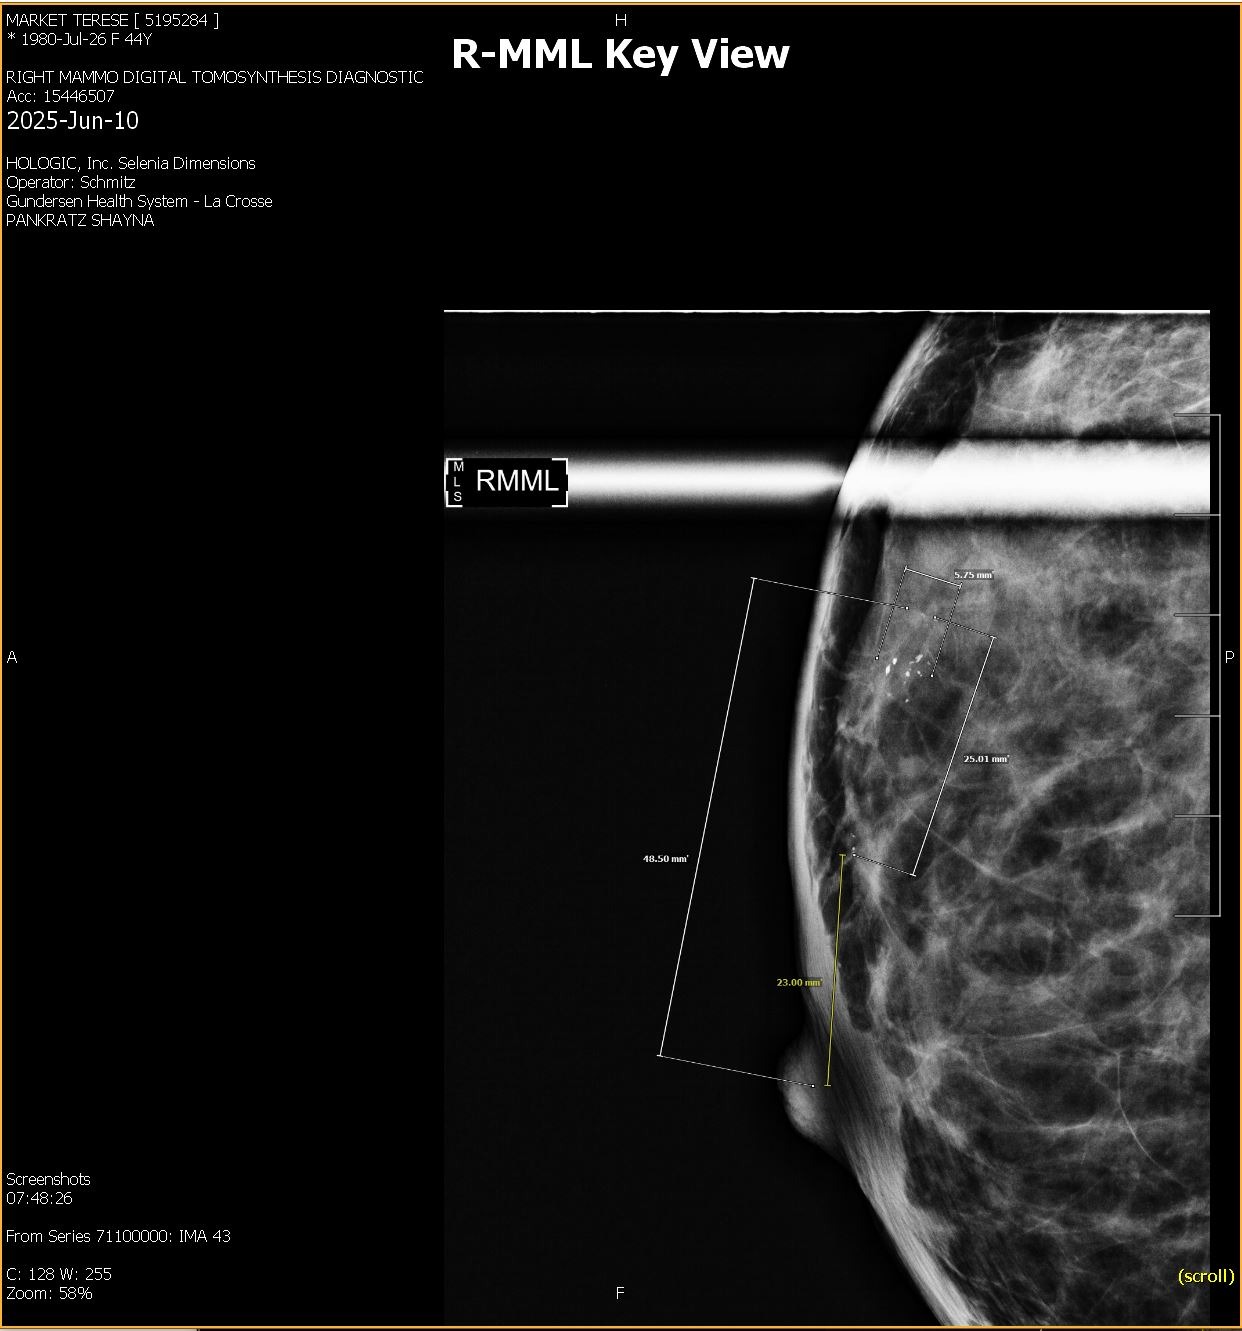

In late May 2025, after an insurance change, I scheduled a routine mammogram and was able to get one the same day. Two days later, I was notified of abnormal results. After a diagnostic mammogram and biopsy, I was diagnosed with DCIS—Stage 0 breast cancer, grade 2. An MRI later confirmed the diagnosis and showed a broader area of concern. This all happened just weeks before I competed at APO Nationals in powerlifting, which I went on to complete before beginning the next phase of appointments and planning. Because I qualified for APO Worlds, my oncologist and I agreed it was reasonable to delay a double mastectomy until after November while managing the cancer with medication. Training and competing during treatment was extremely difficult, but I did it.